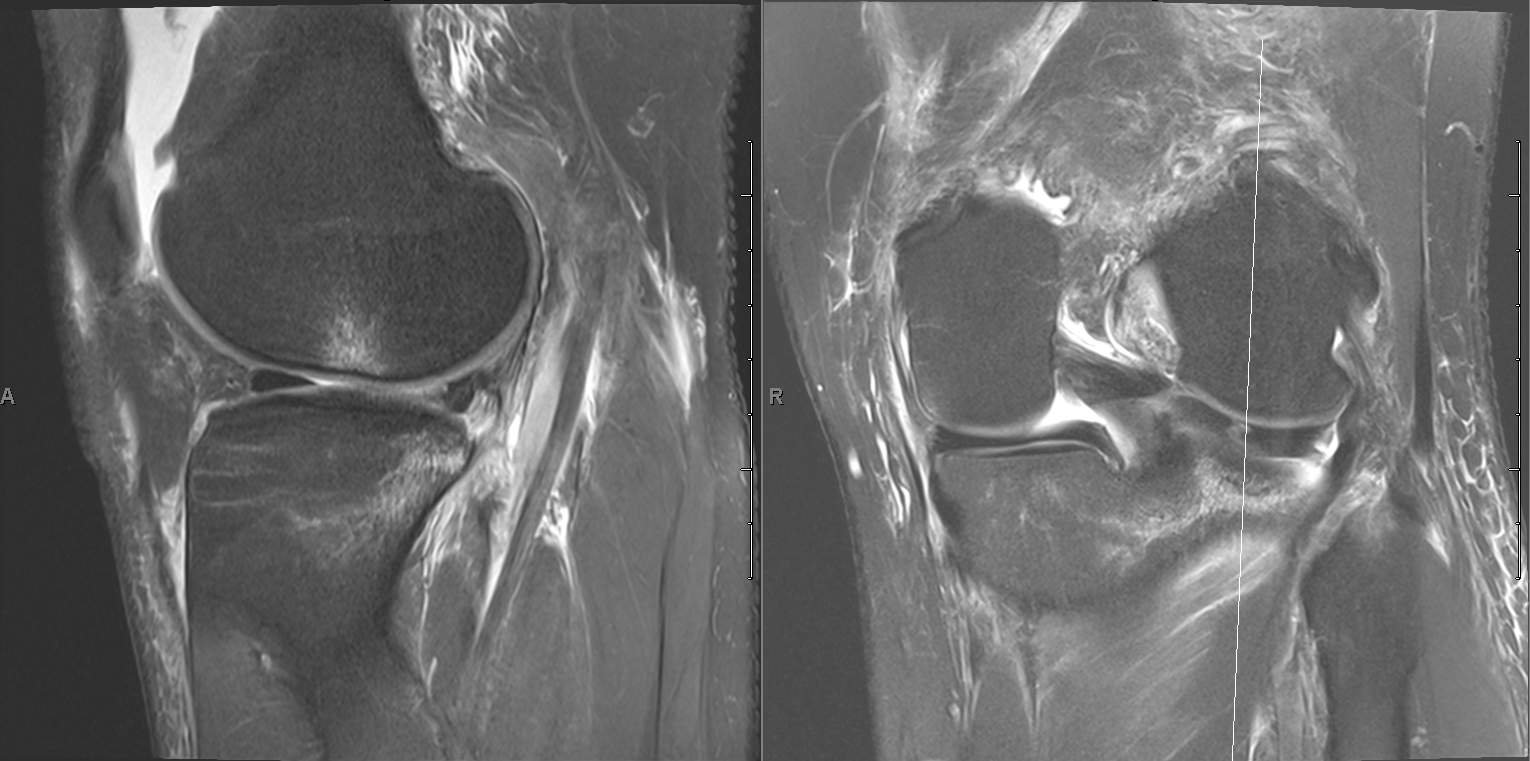

ACL tear Radiology at St. Vincent's University Hospital Acl Injury X Ray Findings Acl tears are common athletic injuries leading to anterior and lateral rotatory instability of the knee. Diagnosis can be suspected clinically with presence of a traumatic knee. Acl tears typically occur in the middle portion of the ligament (midsubstance tears) and appear as discontinuity of the ligament or abnormal contour. In acute or subacute injury, thickening and oedema of the.. Acl Injury X Ray Findings.